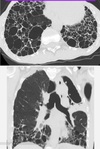

1

Not at all